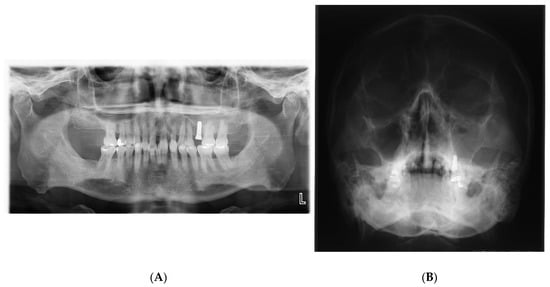

The possible causes of chronic maxillary sinusitis after dental implantation caused by surgeons include sinus penetration by the implant (Figure 2), perforation of the Schneiderian membrane during the sinus lift, and so on [3]. However, maxillary sinusitis rarely occurs after sinus penetration by implant or perforation of the Schneiderian membrane during a sinus lift, because the implant body or bone graft is sterilized and clean [8]. Therefore, it is not clear whether sinus penetration by the implant or perforation of the Schneiderian membrane during a sinus lift is a possible factor predisposing the patient to maxillary sinusitis after dental implantation.

Figure 2. (A) During implant placement, the surgeon pierced the maxillary sinus mucosa, and the postoperative panoramic photograph shows that the implant body slightly protrudes into the left maxillary sinus floor; (B) 7 days after the operation, the upper left maxillary sinus was opaque, suggesting acute left maxillary sinusitis. (unpublished data).